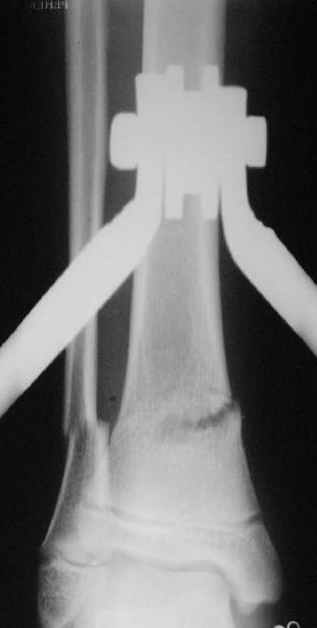

Перелом костей н\3 правой голени со смещением. Перелом большеберцовой кости можно охарактеризовать как компрессионно-оскольчатый.

Скелетное вытяжение за пяточную кость.

В январе 2005: варусная деформация н\3 голени, болевой с-м, комбинированная контрактура г\стопного сустава, нейропатия м\берцового нерва сохраняется слабость разгибания 1 пальца.

Первичные

Вытяжение